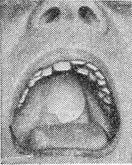

![]() Плаваючий обтуратор неба. |

Просвіти при уроджених ущелинах піднебіння заповнюють так званим плаваючим, тобто рухомим, О. (рис. 1) - тонкою пластинкою, потовщені краї якої седлообразно захоплюють краю твердого піднебіння, а задня частина утримується кільцем скорочувальних м'язів м'якого піднебіння і задньої стінки глотки. Задня частина плаваючого обтуратора повинна бути сформована у відповідності з положенням і рухами м'язів м'якого піднебіння і задньої стінки глотки. Доцільно застосувати плаваючий О. до прорізування зубів (вже в перші дні після народження) (рис. 2). Це оберігає дітей від запальних ускладнень у дихальних шляхах, слухових трубах і середньому вусі і створює майже нормальні умови для розвитку правильної вимови.

Рис. 2. Плаваючий обтуратор для дитини до прорізування зубів (на гіпсовій моделі).